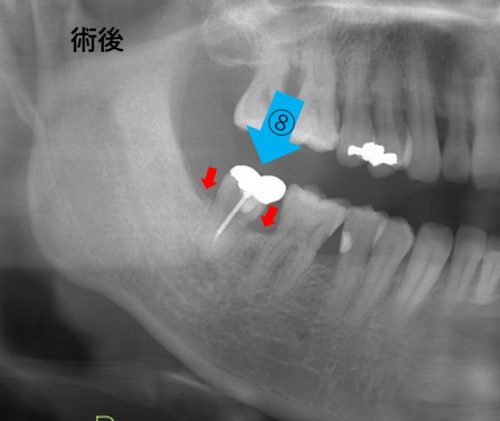

201.親知らずの移植!歯周病の歯を救え!

歯周病 小矢部―砺波 渡辺歯科医院